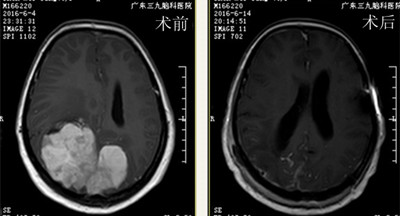

▲术前术后MR对比